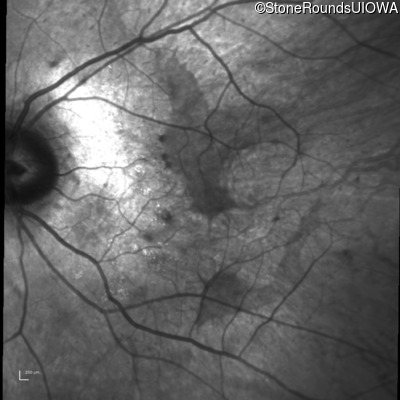

Infrared Fundus Photograph - Right - 20/50 sc

Exemplar